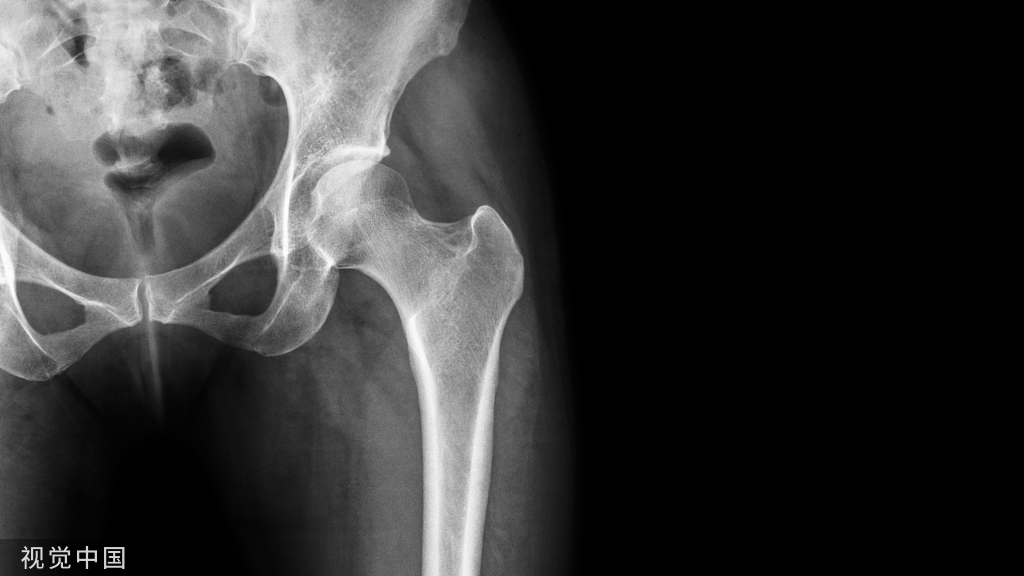

骨性结构

肱骨远端

– 冠突窝、鹰嘴窝、桡骨头窝

– 肱骨滑车:300 ° 关节面

– 肱骨小头:180 °关节面

– 内外上髁:肌肉、韧带

桡骨近端

• 桡骨头:40 °弧

• 桡骨颈:与骨干成15 °角

• 桡骨粗隆:头下2.5-3cm;前滑囊,后肌止点

尺骨近端

• 鹰咀:180 °半月切迹,与骨干成30 °角,肱三头肌止点

• 冠突:最重要骨性稳定结构

• 尺骨粗隆:肱肌止点

• 桡切迹:70 °,冠突下方

• 骨干:1-6 °外翻,参与提携角

• 后方:旋后肌嵴